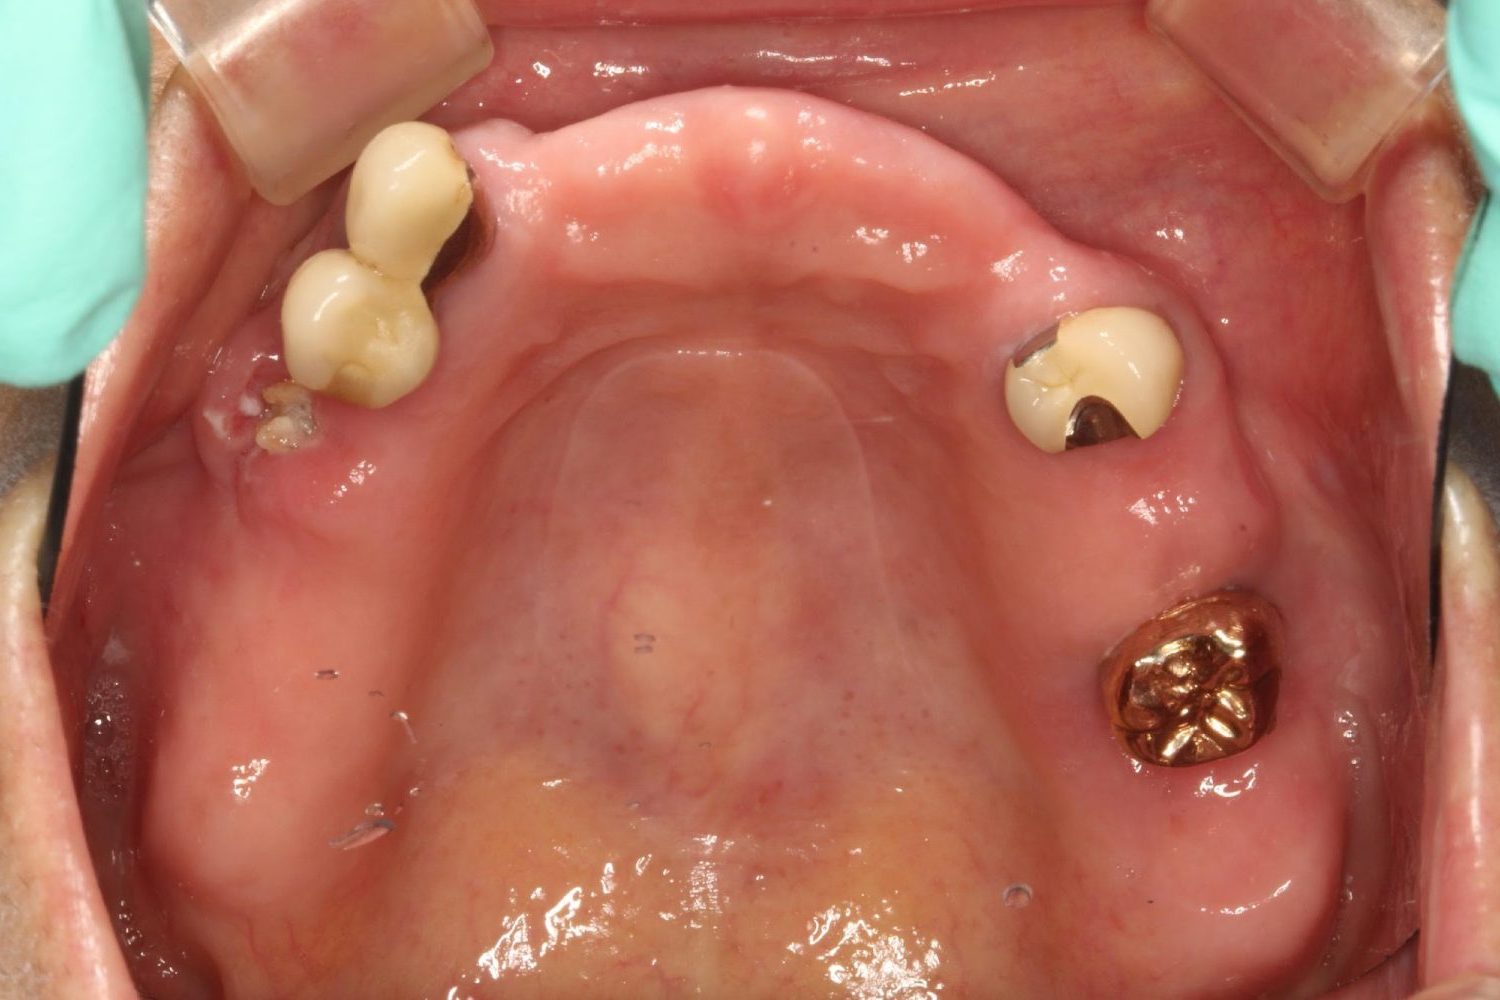

インプラント治療の症例紹介④

Before

After

主訴

義歯による疼痛

治療内容

下顎舌側に骨隆起があり義歯困難な状態。保存不可能な歯の抜歯を行い、インプラントを埋入し咬合再構成を行った。

治療費

2,851,200円(税込)

治療期間

29ヶ月

通院回数

26回

想定されたリスク

※咬合力の強い方なので、予防的にマウスピースの装着が必要。インプラント周囲炎の恐れがありました。

歯の欠損の対合歯の挺出等を修正し咬合平面を揃え咬合再構成を行った症例。